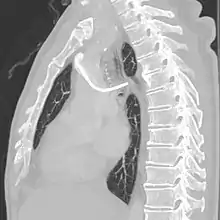

Follow-up chest X-ray after insertion of a port, with a malpositioned tip in the azygos vein.

CT scan confirming a tip in the azygos vein.

A port is most commonly inserted as an outpatient surgery procedure in a hospital or clinic by an interventional radiologist or surgeon, under moderate sedation. Implantation is increasingly performed by interventional radiologists due to advancements in techniques and their facile use of imaging technologies. When no longer needed, the port can be removed in the interventional radiology suite or an operating room. Fluoroscopy is useful in guiding the insertion of ports.[4]